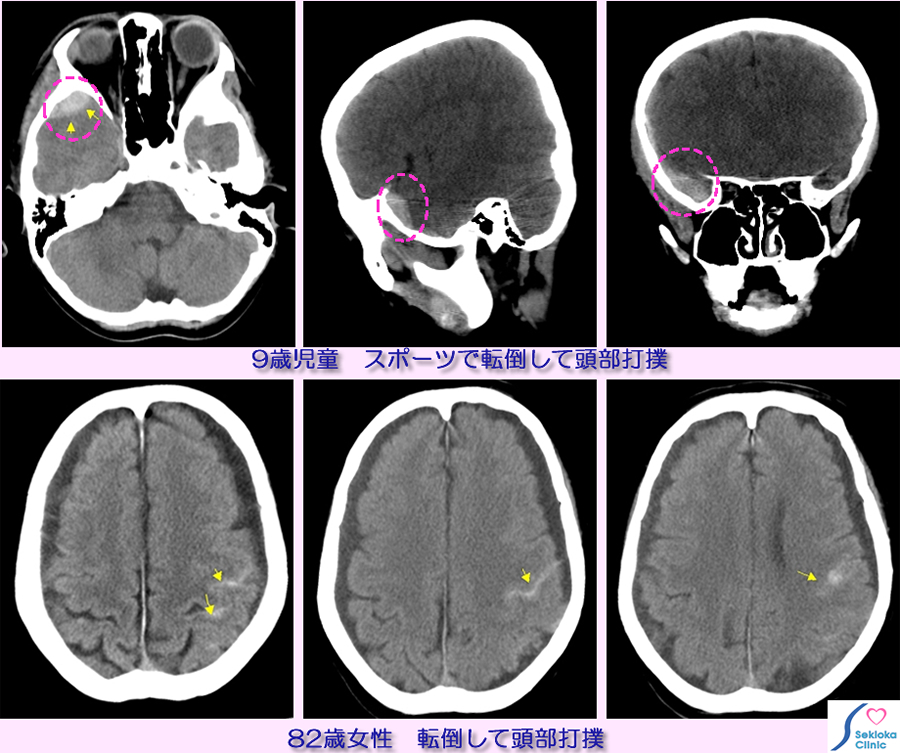

上段は 9歳の男児、運動時転倒して頭部打撲。その2時間後、頭痛に加え、吐き気が出現し受診。

下段は82歳女性、路上で転倒し頭部打撲。その数時間後、起立、歩行障害、軽度の意識障害も出現し、救急車で来院。

CT検査で出血部位は高X線吸収部位(画像では白く表示)として検索される。出血の部位、大きさ、頭蓋骨折の有無など評価

掲載例は血腫が小さく、入院にて経過観察のみで治療。